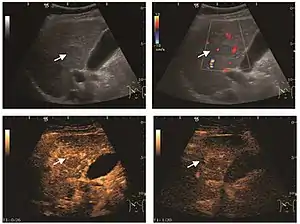

HCC appearance on 2D ultrasound is that of a solid tumor, with imprecise delineation, with heterogeneous structure, uni- or multilocular (encephaloid form). An "infiltrative" type is also described which is difficult to discriminate from liver nodular reconstruction in cirrhosis. Typically HCC invades liver vessels, primarily the portal veins but also the hepatic veins . Doppler examination detects a high speed arterial flow and low impedance index (correlated with described changes in tumor angiogenesis). The spatial distribution of the vessels is irregular, disordered. CEUS examination shows hyperenhancement of the lesion during the arterial phase. During the portal venous phase there is a specific "wash out" of ultrasound contrast agent (UCA) and the tumor appears hypoechoic during the late phase. Poorly differentiated tumors may have a stronger wash out leading to an isoechoic appearance to the liver parenchyma during portal venous phase. This appearance was found in approx. 30% of cases. The described changes have diagnostic value in liver nodules larger than 2 cm.